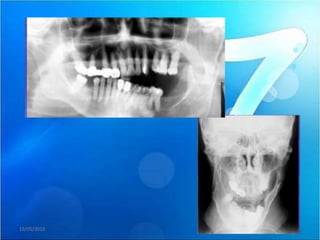

En la radiografía panorámica observamos la alteración morfológica de ambos

cóndilos mandibulares y la presencia de imágenes radiopacas hacia medial de

ambas articulaciones compatibles con probables fragmentos óseos libres.

Se le realiza el estudio de tomografía volumétrica, las imágenes

axiales y coronales muestran zonas erosivas en ambos cóndilos

mandibulares, e imágenes hipodensas compatibles con probable

quiste subarticular.

En las secciones sagitales observese la disminución del espacio articular, el

aplanamiento y esclerosis de las superficies articulares y la disminución del

recorrido de los cóndilos (vista sagital a boca abierta) ,observamos la

presencia de osteofito (proyección ósea anterior), asi como imágenes

hiperdensas anteriores al cóndilo mandibular compatibles con cuerpos libres

intraarticulares.

• En la vista

panorámica

de la

articulación

con radiologia

convencional

se observan

imágenes

radiopacas en

la articulación

del lado

izquierdo

(flecha)